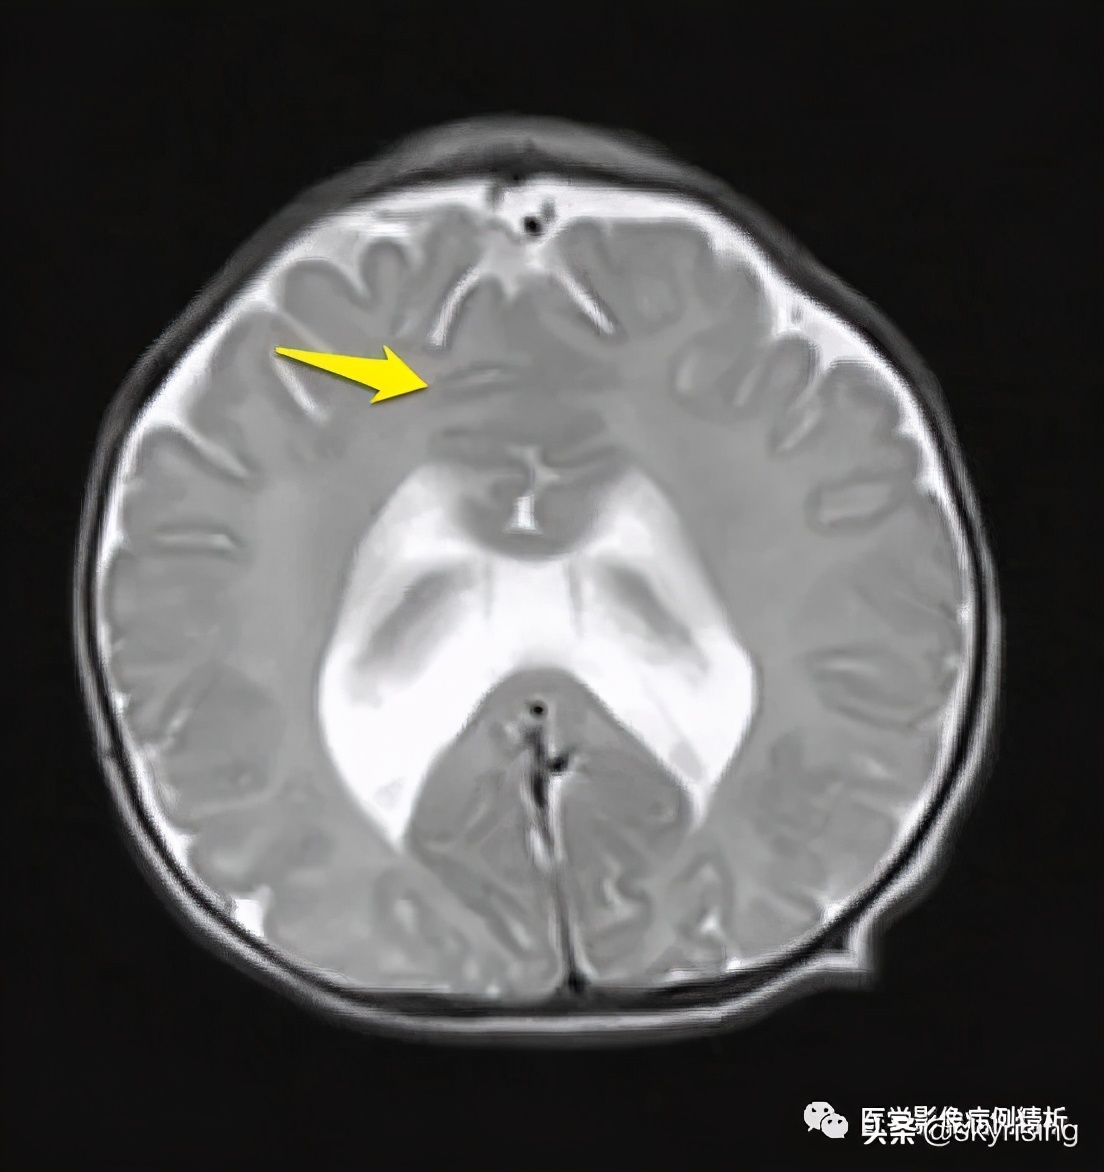

T1WI轴位像:黄色箭头所示可见大脑前纵裂缺如,双侧额叶脑实质融合,胼胝体膝部未见显示。透明隔缺如,双侧侧脑室融合呈蝙蝠翼样改变。侧脑室额角未见显示,体部平行于矢状线,后角失去张力、变尖。

黄色箭头所示为大脑前动脉单支血管影,被推移至融合脑实质前。枕角形态尚可。双侧额部蛛网膜下腔增宽,见细带状液体信号,提示硬膜下积液。

红色箭头所示为融合额叶脑实质,大脑纵裂不完全。白色箭头所示为双侧视神经,形态对称、大小、信号未见异常,提示视神经发育正常。